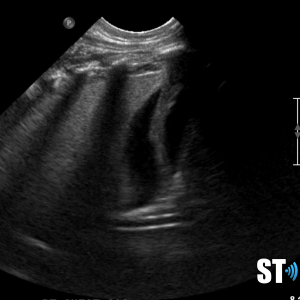

Normal lung ultrasound shows a clean linear pleural line with A-lines (multiple horizontal reverb artifacts) and lung sliding with respiration.

A-lines

Horizontal reverb artifacts at equidistant intervals from pleural interface.

B – lines

Vertical comet-tail reverb artifacts that extend to the bottom of the screen which may be normal (1-2 per intercostal space) or indicative of alveolar interstitial fluid (3 or more B- lines in multiple locations).